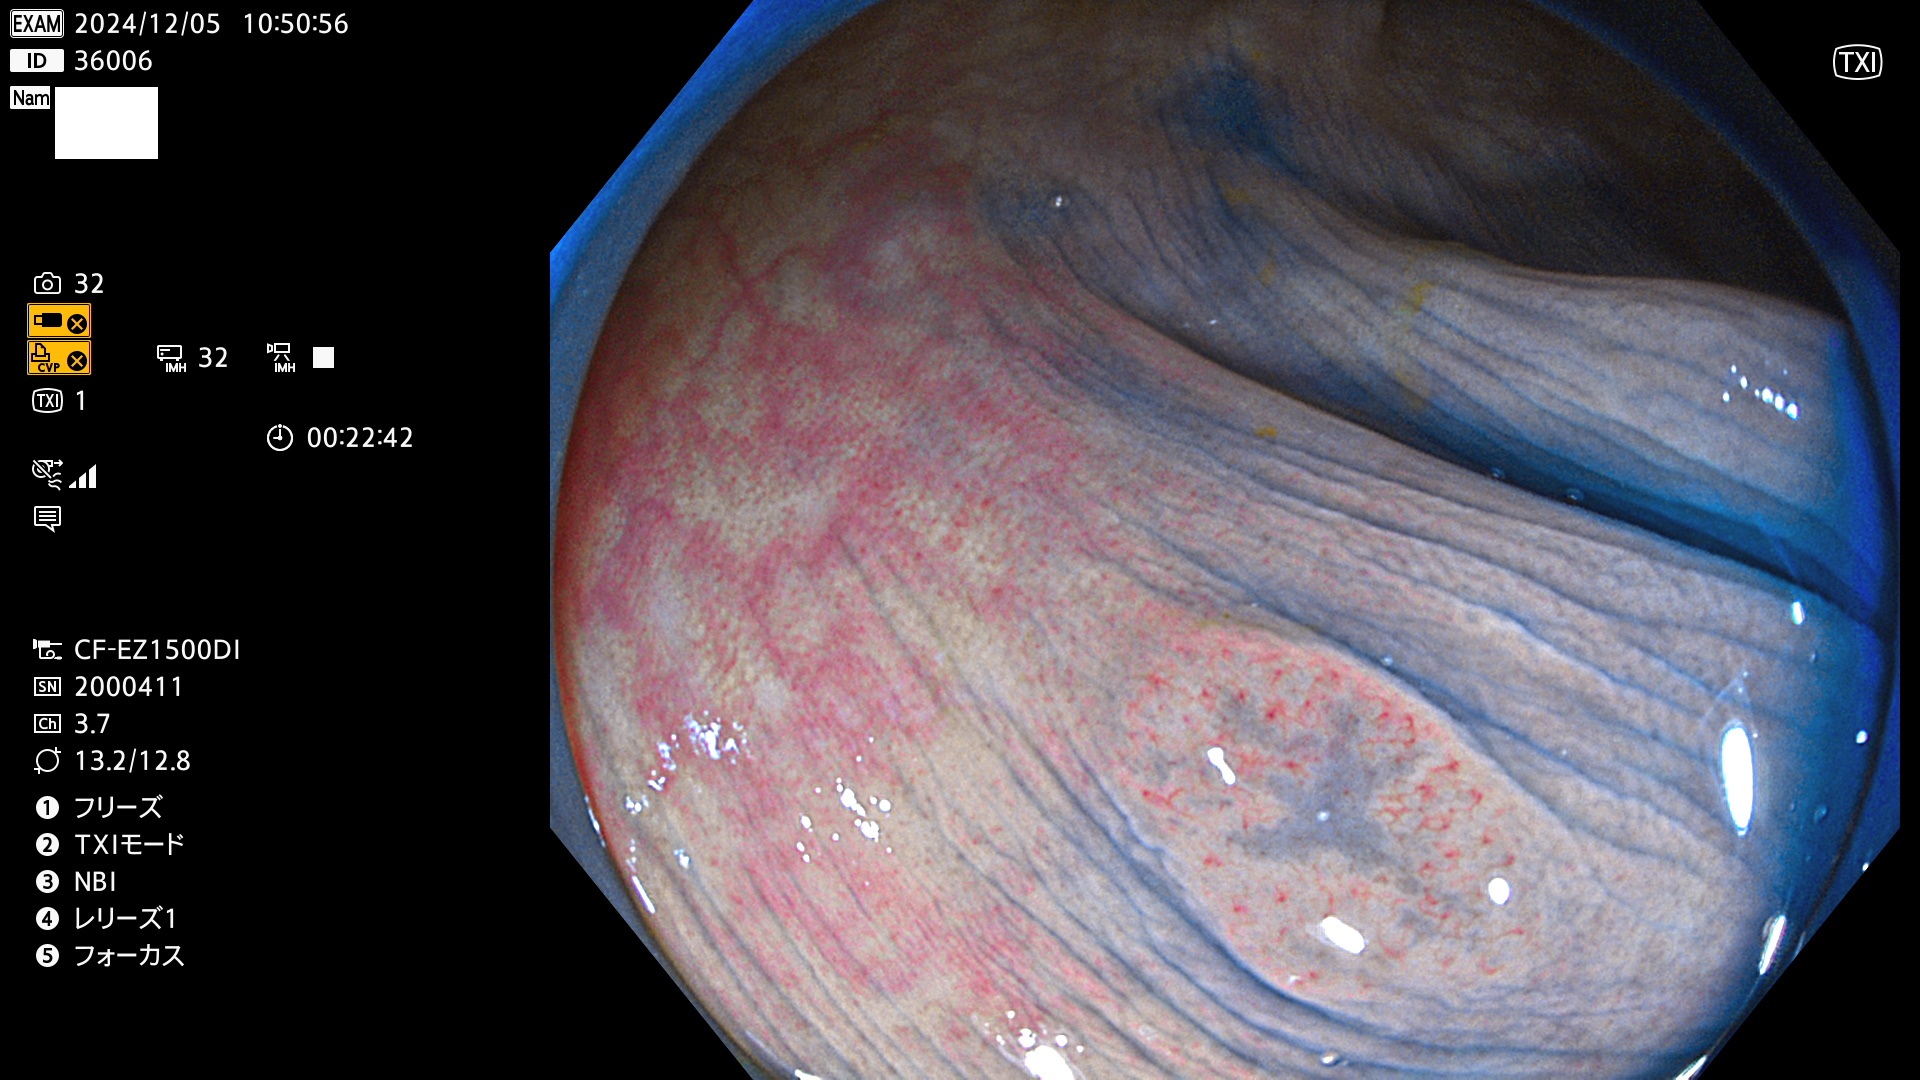

今週のUb、Uc型腺腫

完全に平坦な物をUb、陥凹している物をUcと呼びます。最も発見が難しく危険な病変です。

毎週の検査(木・金・土・日)に発見されたUb、Uc型・腺腫を、その週の日曜の夜にUPし1週間、提示します。

抽出の対象期間 2024年12月5日〜12月8日の4日間(48件の検査)4件 (4/48=8%)